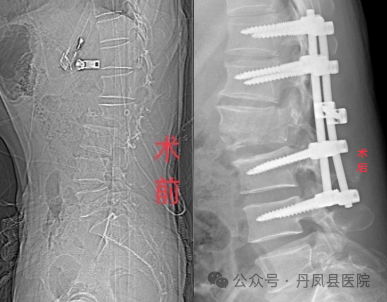

据悉,49岁的何先生因骑三轮车不慎摔伤,伤后即感腰部疼痛剧烈,翻身困难,不能站立,双下肢活动障碍,会阴部感觉丧失,双下肢感觉麻木,排大小便障碍,被家人紧急送至我院骨三科救治。科室值班医生何正位大夫立即为患者进行查体,经查体,发现患者腰部压痛,以腰1、2棘突压痛明显,腰部主被动活动受限,双下肢活动、感觉障碍,且不时叫嚷腰部疼痛,神情十分痛苦。临床经验丰富的何大夫进一步为患者进行腰部CT和磁共振检查,诊断为:腰2椎体爆裂骨折、滑脱并椎管Ⅲ度狭窄,腰1椎体压缩性骨折。 ![]()

何医生介绍到:“患者腰2椎体为爆裂性骨折,累及椎体的前柱、中柱和后柱,已经严重压迫到周围神经,因受损椎体及相应节段脊髓受压,导致患者下肢无法活动,受损腰椎如不及时手术固定,腰椎周围神经受压会持续加重,不但影响治疗,还极易给患者造成二次伤害,但患者腰2椎体周围神经丰富,若手术中稍有不慎,甚至造成患者瘫痪,手术风险高,难度大。一刻也不能耽搁,必须尽快确定手术方案,当时就立即向科主任汇报了患者的情况。”虽在元旦假期,张丹生主任立即赶至病房查看了患者。为了尽快解除脊髓压迫、减轻骨折二次伤害,张丹生主任立即组织科室团队为患者研究手术方案,从围术期管理、术中操作、术后护理及康复等方面下手,精心设计手术、护理方案,制定了利用脊柱钉棒系统为患者固定创伤腰椎、解除脊髓压迫的手术方案。通过手术不但能解除腰椎骨折对神经的压迫,还能恢复患者脊柱正常形态,一般术后三个月时间即可完全康复。经家属同意后,当日晚上,张丹生主任带领骨科团队成功为患者实施了腰椎钉棒系统内固定、全椎板减压、神经探查、关节突植骨术,整个手术历时两小时,过程顺利。术后第一天,患者明显感觉到双下肢肌力恢复,大小便正常,会阴区感觉恢复,治疗效果令患者及家属几乎不敢相信真相,激动地说:“我以为这么复杂的腰椎手术,咱县医院做不了咧,结果做的这么完美,以往的这种手术基本都要往西安大医院跑,花钱多还折腾人!你们真是解决了老百姓的看病难、看病贵的问题!”![]()

目前患者术后已经一周余,恢复良好,再次放射拍片复查,脊柱胸腰段生理曲度恢复正常,受损椎体高度恢复满意,狭窄的椎管腔已扩大至正常范围,突入椎管的骨块回纳良好,手术效果非常满意。